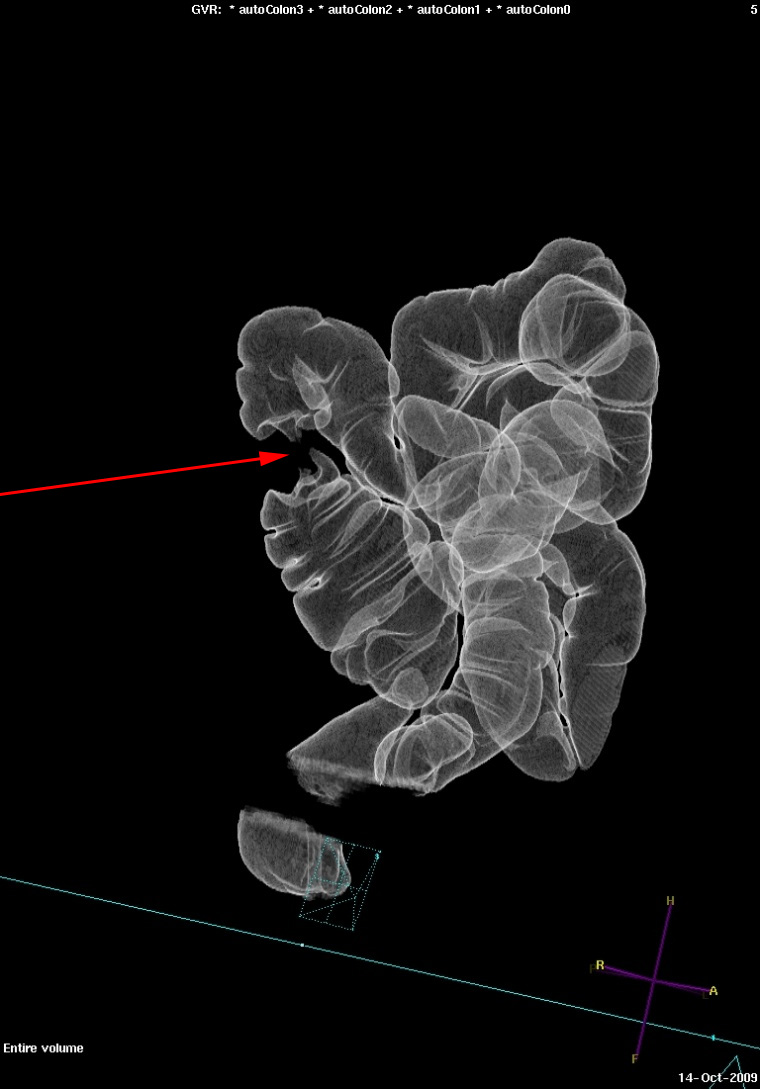

3D rekonstruktion der viser tumoren (rød pil) i colon ascendens. Samme patient som på de to illustrationer ovenfor.